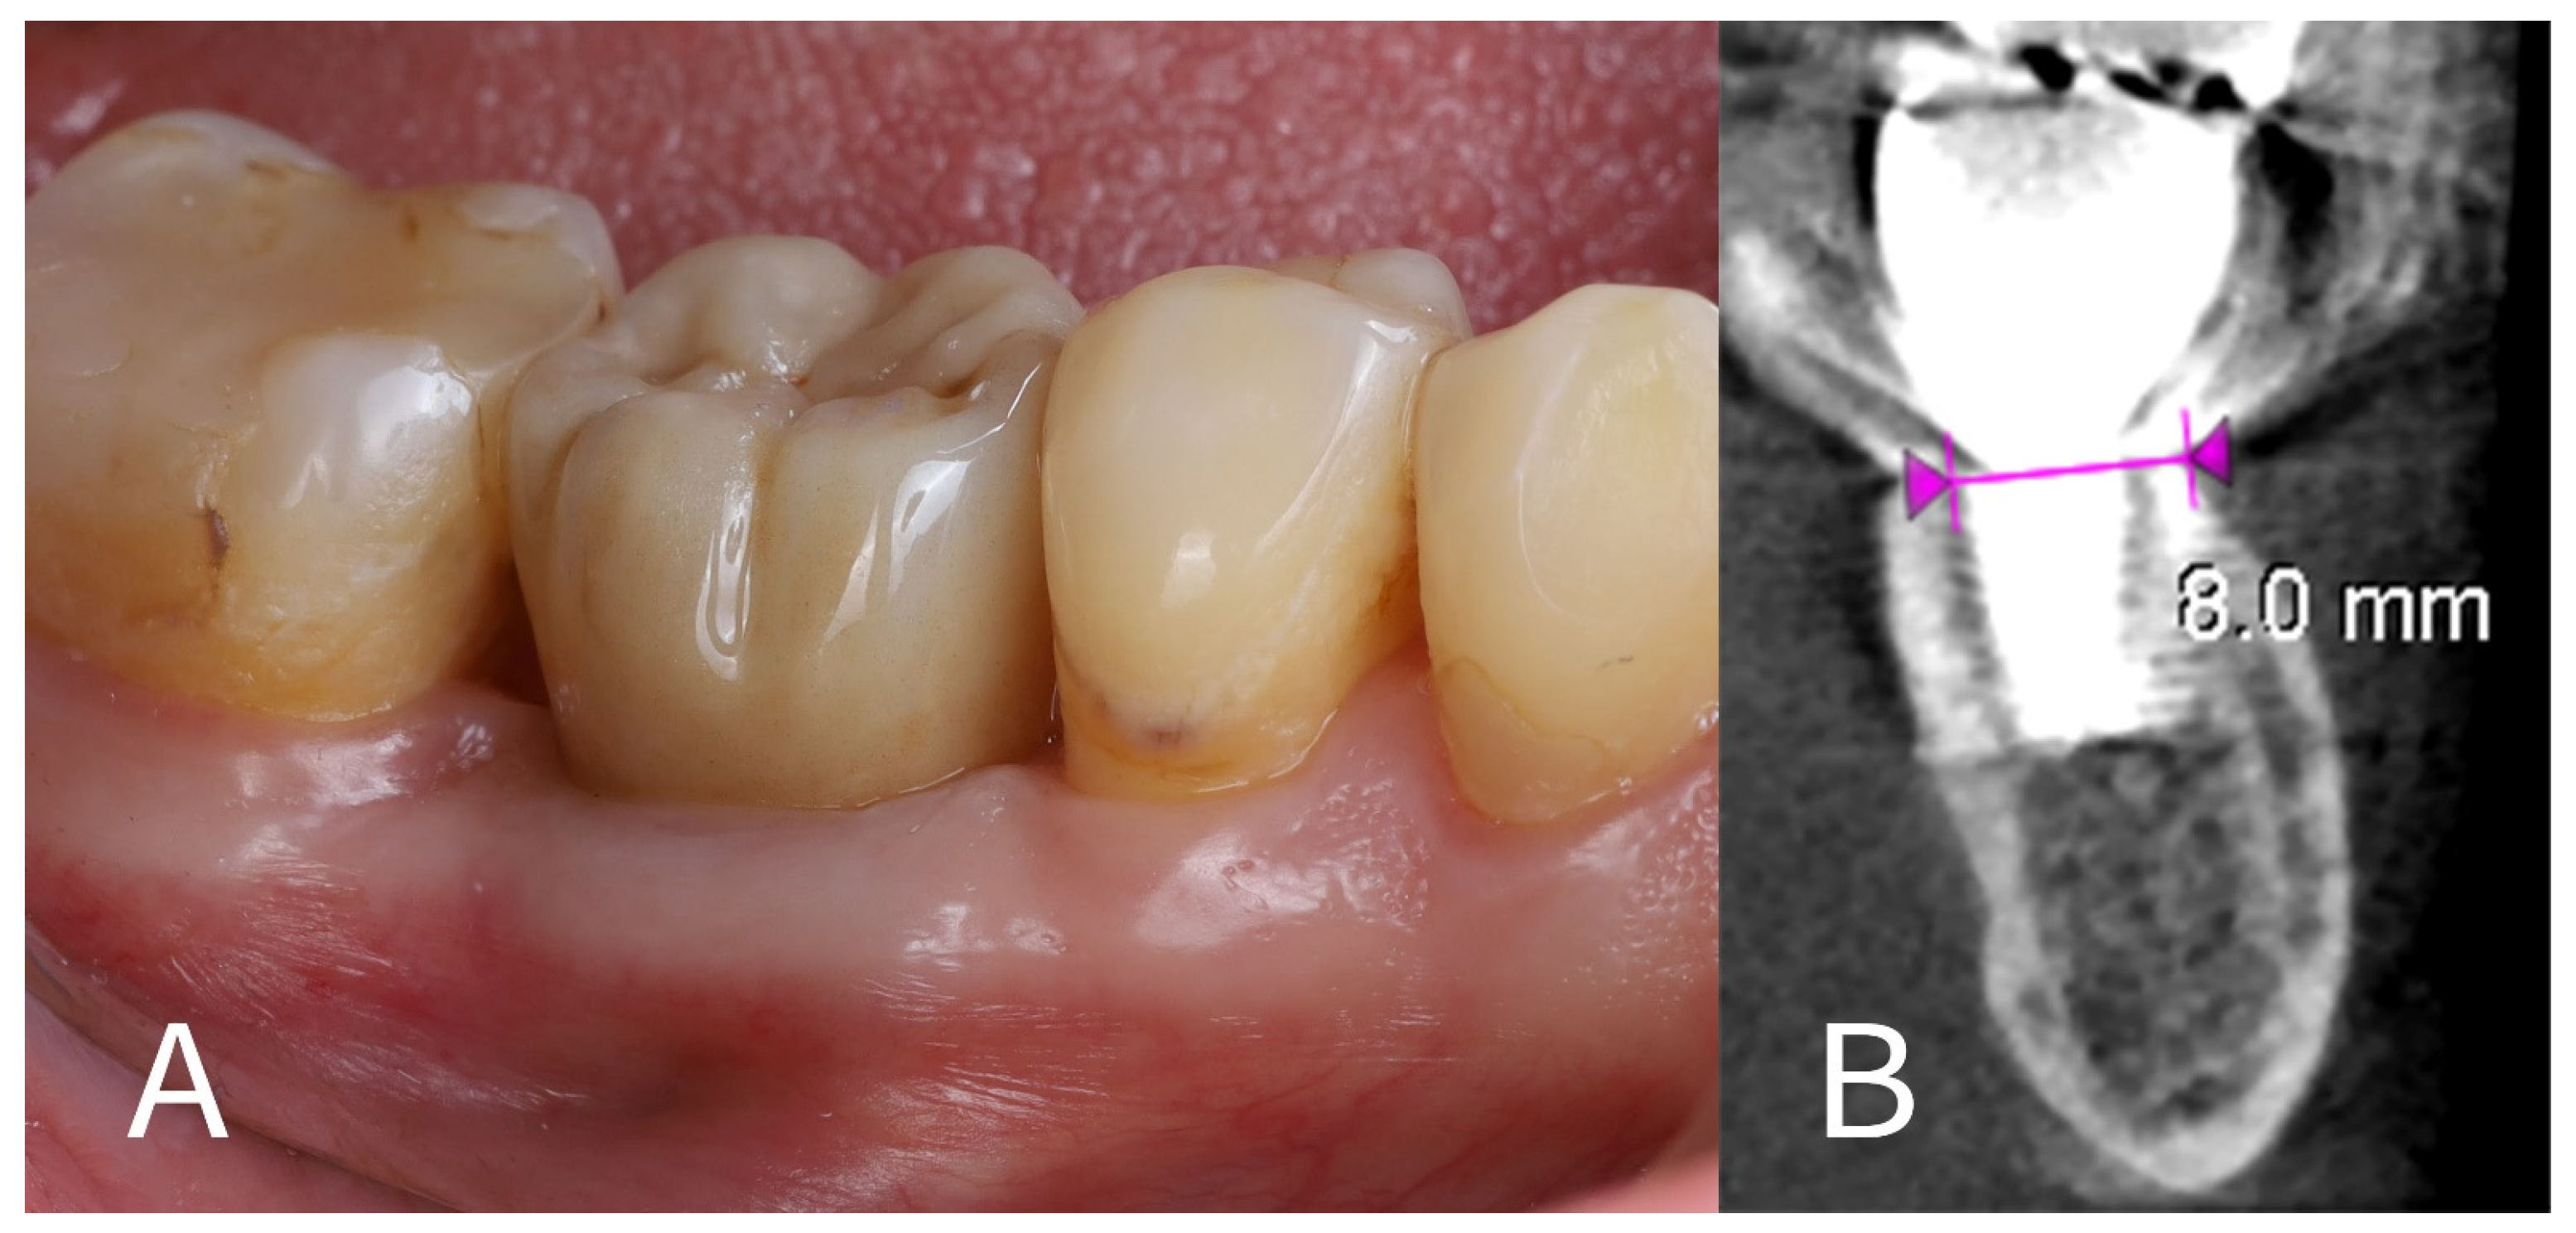

- Prosthetic rehabilitation: At approximately 4 months after the extraction and implant placement, the site was restored with a permanent prosthesis. A screw-retained monolithic full-contour zirconia crown (KATANA Zirconia™ YML, Kuraray Noritake Dental Inc., Tokyo, Japan) was fabricated and attached to the implant (Figure 8A). The crown was designed to have an emergence profile that matched the contour shaped by the healing abutment and surrounding tissue, thereby maintaining the ridge profile.

- One-year follow-up: The patient was re-examined again at 12 months post-implant placement (roughly 8 months after crown delivery). The patient reported excellent function with the implant and no discomfort. A final CBCT scan at 1 year showed that the alveolar ridge dimensions were unchanged from the 4-month scan (Figure 8B). The horizontal dimension of the buccal bone had an additional resorption of only ~0.1 mm between the 4-month and 12-month time points, indicating stable hard tissue conditions. The buccal plate remained intact and fully supported the implant. The peri-implant soft tissues were healthy, with no signs of recession or inflammation around the crown. The overall result at 1 year was a stable implant with well-preserved surrounding tissues, fulfilling both functional and aesthetic expectations for a posterior implant site.